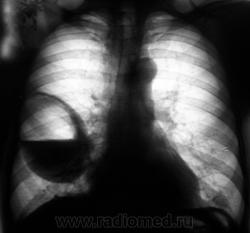

Лаборант «с флюорографа» пригласил посмотреть произведенную флюорограмму.

Лаборант «с флюорографа» пригласил посмотреть произведенную флюорограмму.роизвели рентген

Произвели рентгенографию в стандартных проекциях.

Флюорограмма 2009 года.

сильно похоже на нагноившуюся кисту...

Она и есть.

Но, пациент жалоб не предъявляет...

Киста, точно киста. Был пациент на консультации у торакальщиков, будут готовить к плановой операции.